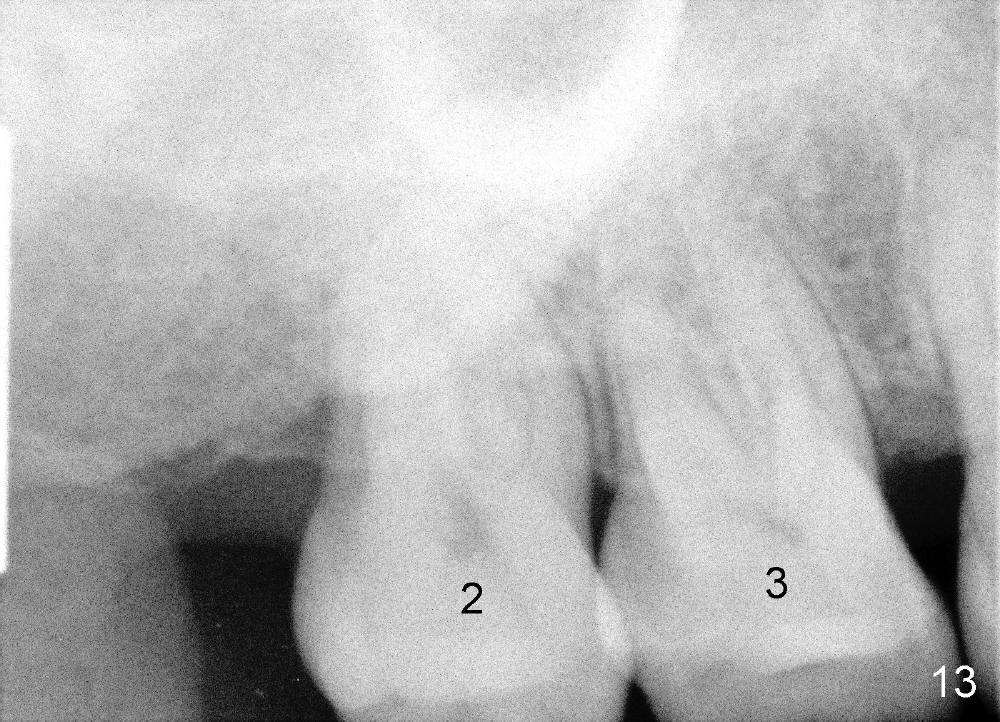

Fig.12-16 are taken 9 months after the orthodontic treatment. The lamina dura appears to form mesial and distal to the implant at the site of #30 (white arrowheads). There is no gross bone resorption associated with orthodontically moved teeth (Fig.12,13: #2,3,31). The posterior overjet remains normal (Fig.14). The arrowheads in Fig.15 indicate a worn facet, which was caused by the previous abnormal overjet (Fig.2). The alignment of the upper right quadrant also remains normal. The patient wears suction down retainers. He is pleased with improvement of mastication.